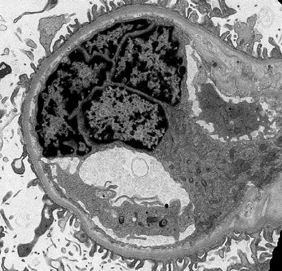

With the rapid development of self-supervised learning (e.g., contrastive learning), the importance of having large-scale images (even without annotations) for training a more generalizable AI model has been widely recognized in medical image analysis. However, collecting large-scale task-specific unannotated data at scale can be challenging for individual labs. Existing online resources, such as digital books, publications, and search engines, provide a new resource for obtaining large-scale images. However, published images in healthcare (e.g., radiology and pathology) consist of a considerable amount of compound figures with subplots. In order to extract and separate compound figures into usable individual images for downstream learning, we propose a simple compound figure separation (SimCFS) framework without using the traditionally required detection bounding box annotations, with a new loss function and a hard case simulation. Our technical contribution is four-fold: (1) we introduce a simulation-based training framework that minimizes the need for resource extensive bounding box annotations; (2) we propose a new side loss that is optimized for compound figure separation; (3) we propose an intra-class image augmentation method to simulate hard cases; and (4) to the best of our knowledge, this is the first study that evaluates the efficacy of leveraging self-supervised learning with compound image separation. From the results, the proposed SimCFS achieved state-of-the-art performance on the ImageCLEF 2016 Compound Figure Separation Database. The pretrained self-supervised learning model using large-scale mined figures improved the accuracy of downstream image classification tasks with a contrastive learning algorithm. The source code of SimCFS is made publicly available at https://github.com/hrlblab/ImageSeperation.